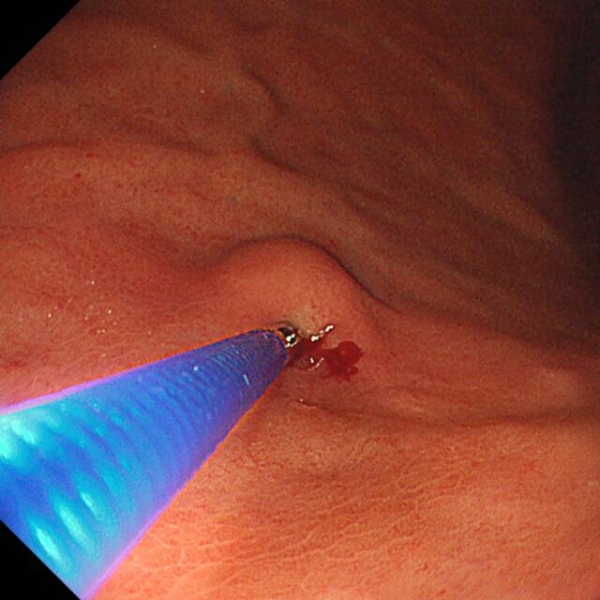

在检查过程中,若发现高度怀疑早癌或诊断不明确的病灶,及时与患者家属沟通,经同意后,进行精准靶向活检。避免对典型良性病变或计划行诊断性ESD/EMR的浅表癌进行活检。

运用奥林巴斯X1设备及高清放大内镜,针对可疑区域精准取样,检出率大幅提升。

活检则是医生手中的另一把“利器”

为疾病的最终确诊提供“金标准”